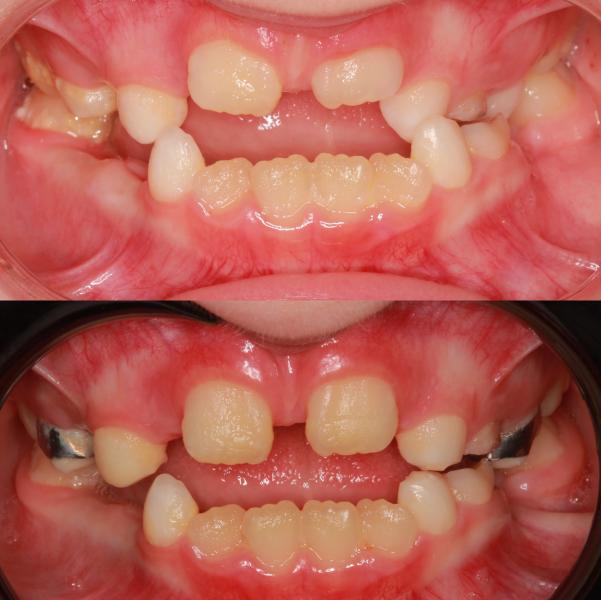

Ребёнок 👧🏼 А 7,5 годиков 🐥😹.

Жалобы родителей «Зубы не прорезываются, неправильный прикус, ассиметрия нижней челюсти».

Лечение решила проводить на несъёмной технике с помощью аппарата #маркоросса

Какие изменения мы получили в ходе расширения верхней челюсти ?